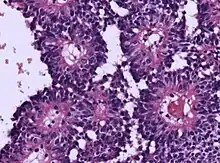

Micrograph of an astroblastoma showing the characteristic nuclear pervivascular pseudorosette. H&E stain.

• Radial arrangement as a pseudorosette